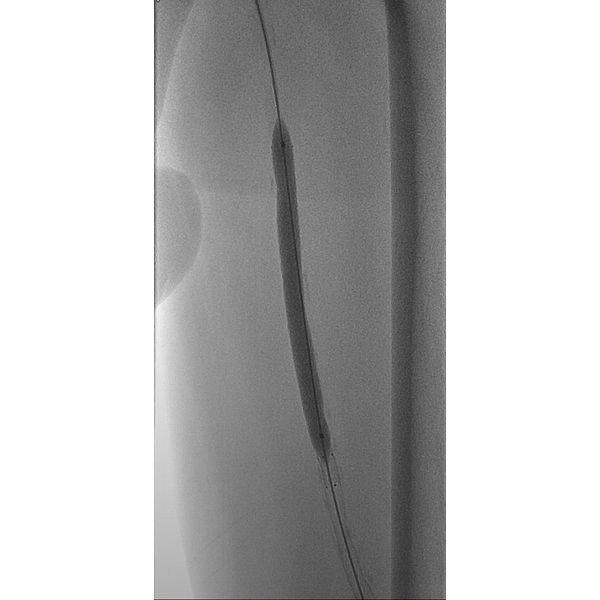

Пациенту провели транслюминальную баллонную ангиопластику магистральных (крупных) артерий левой ноги со стентированием поверхностной бедренной артерии. В ходе операции мужчине в закупоренную артерию ввели баллонный катетер, чтобы расширить её, и установили специальный каркас, который поддерживает просвет сосуда и нормальный кровоток. После этого ему провели некрэктомию — удалили отмершие ткани на стопе.

Через полтора месяца эту процедуру повторили и затем установили вакуумную систему, чтобы обеспечить необходимые условия для заживления раны и образования новой, грануляционной ткани.